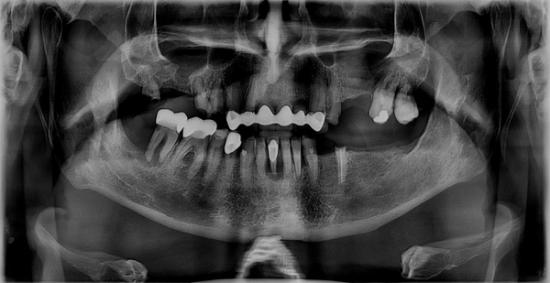

After Photo